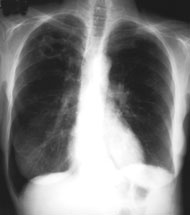

Eine 70-jährige Patientin meldet sich bei Ihnen in der Praxis mit Verschlechterung des Allgemeinzustandes seit 4-5 Wochen und Fieber bis maximal 38.5 Grad.

Des weitern klagt sie über einen trockenen Husten. Ausser einer arteriellen Hypertonie besteht als Vorerkrankung eine leichte COPD. Da Sie ausser dem Husten keinen klinischen Fokus für einen Infekt finden, entschliessen Sie sich für ein Thorax-Bild. Optimalerweise haben Sie sogar noch ein pa-Thorax von vor 2 Jahren zum Vergleich: